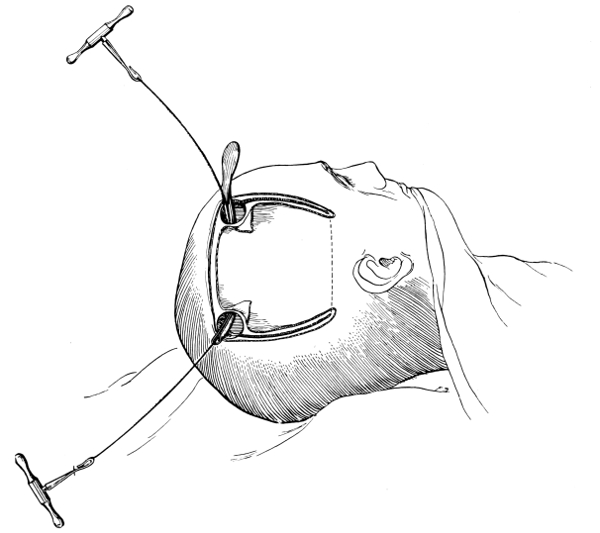

THE CONTROL OF HÆMORRHAGE

All surgeons must have appreciated the difficulty attendant on the application of forceps to, and the ligature of, divided scalp-vessels. The patient may lose a considerable quantity of blood, and much valuable time will be wasted before the more essential part of the operation is commenced. All this can, under ordinary circumstances, be avoided by the use of the scalp-tourniquet. As used by Cushing it consists of a rubber ring fashioned after the style of an Esmarch’s tourniquet, encircling the head and passing from the lower frontal region in front, above the ears, to the lower occipital region behind. A median tape, passing from glabella to occiput, prevents any tendency for the tourniquet to slip down over the eyes, at the same time acting as a convenient landmark for the superior longitudinal sinus.

The tourniquet, when applied with the correct pressure, should, under ordinary circumstances, completely control all hæmorrhage from the divided scalp-vessels. It should be noted, however, that[14] bleeding will be rather increased than otherwise if the tourniquet be so loosely applied as to impede the venous return without compressing the scalp arteries. A little experience will soon enable the operator to gauge the requisite pressure.

Fig. 4. The Scalp-tourniquet. Front View.

Fig. 5. The Scalp-tourniquet. Back View.

There is one other exception to the satisfactory working of the scalp-tourniquet. In the presence of a superficial cerebral tumour, especially when of a malignant nature, the normal communication between the intra- and extra-cranial vascular systems may be so exaggerated that those scalp-vessels which receive diploic and emissary venous communications will give rise to some trouble. This difficulty should be overcome—not by rapidity in the formation[15] and turning down of the flap—but by clipping each vessel as exposed or divided, by the application of pressure and by foraminal occlusion (see also p. 17).

I found Cushing’s tourniquet rather inconvenient in its application, and, after various modifications, am accustomed to use the one depicted in the illustration. It consists of two flat metal bands connected posteriorly by a strong rubber connecting link, the two bands passing in front through a metal fixation piece possessing a screw which, when tightened up, allows of the maintenance of the desired pressure. The median tape, previously mentioned, helps to keep the tourniquet in position.

The tourniquet is applied as follows: the whole head is enveloped in gauze—two or three layers thick, and cut to the size and shape of a large handkerchief. The tourniquet is slipped over the head,[16] as low down as possible, and then tightened up. The median tape, having a loop behind through which the tourniquet passes, is laid in the middle line and tied round the screw on the fixation piece.

The gauze should then be moistened with saline solution or some mild antiseptic, so that it clings tightly to the underlying scalp and becomes sufficiently translucent to allow of the recognition of any underlying landmarks that may have been previously mapped out with the scalpel, iodine, silver nitrate, or aniline pencil.

The scalp-flap is then framed by incisions carried down to the bone, through gauze and scalp, in one sweep. The flap is turned down and covered with gauze. By the adoption of this method hæmorrhage from scalp-vessels is efficiently controlled and the risk of wound infection is reduced to a minimum.